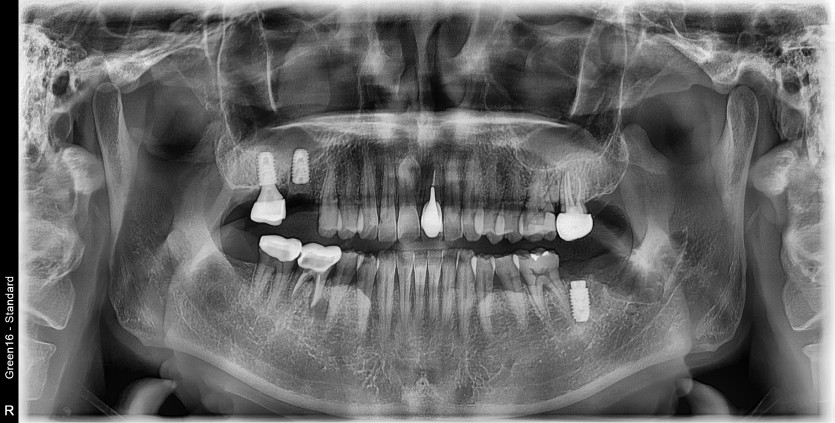

#38 사랑니 발치

#38 사랑니 발치 구강 외과 전문의가 당일 발치했습니다.